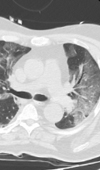

Case Report

Characteristics of Critically Ill Patients with Covid-19: A Cohort Study in Medical Intensive Care Unit (Mulhouse, France)

The outbreak of the novel coronavirus SARS-CoV-2 began in the east of France during the first days of March after a religious meeting gathering about ... Read more

10.36959/856/493